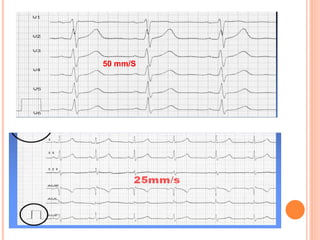

ECG sur papier millimétré déroulé à une vitesse

de 25 mm/ seconde donc 1 mm = 0,04 s

50 mm/S